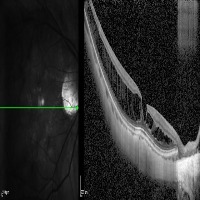

Medical Imaging Analysis: The "three-segment" model can be used by healthcare professionals for enhanced analysis of medical imaging, such as MRI or CT scans. It will help in identifying cleave classes, which can improve detection and diagnosis of potential issues in the brain, particularly those related to retina or neural connections.

Retinal Disease Diagnosis: Ophthalmologists could utilize the model to get help in diagnosing retinal diseases. It can help to identify any abnormalities by differentiating between the 'out', 'in', and 'retina' segments, enabling early detection of conditions such as retinal detachments or macular degeneration.

AI in Surgery: The model can be used to assist surgeons during complex neuro or eye surgeries. It can provide enhanced visualization, enabling real-time differentiation between various segments, leading to more precision in surgical procedures.

Medical Training and Education: The model can be used in medical learning settings, providing students with valuable visual learning material. It could serve as an advanced tool for the understanding of the retina and other segments of the brain or eye.